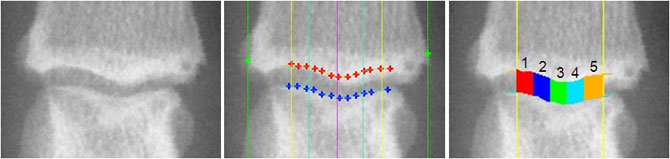

Radiographic JSW at fixed locations |

Hand JSW Measurement Five Measurement regions: JSW1, JSW2, JSW3, JSW4, JSW5 Central JSW measurement: JSWC = (JSW2+JSW3+JSW4)/3 |